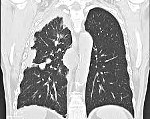

C45.0 Мезотелиома плевры